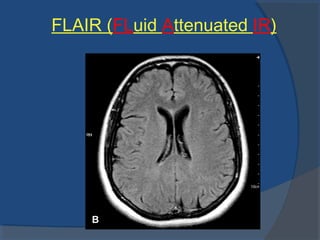

FLAIR (FLuid Attenuated IR)

 Inversion recovery sequence with long TI

 The TI is set to the zero crossing point of fluid→

suppression of signal from csf

 Lesions that are normally covered by bright fluid

signals using conventional T2 contrast are made

visible by FLAIR

FLAIR (Fluid Attenuated Inversion Recovery) Sequence

Thesameprincipleasused for signal suppression of fat

tissuein STIR can also beused to suppresssignal from

CSF. With aTI of around 2000 msthesignal from CSF is

effectively suppressed. An Inversion Timeof 2000 ms. in

combination of along TE isused to study demyelinating

diseases, such asMultipleSclerosis. With thisTI value,

MultipleSclerosislightsup likealight bulb, because

normal fluid issuppressed. FLAIR issubstantially more

sensitivefor demyelinating diseasesthan ordinary T2

weighted sequences

 Evaluation of lesions in periventricularEvaluation of lesions in periventricular

regionregion

 Increased conspicuity of lesions inIncreased conspicuity of lesions in

subarachnoid spacesubarachnoid space

FLAIR

 Multiple sclerosisMultiple sclerosis

 Temporal lobe epilepsyTemporal lobe epilepsy

 Limbic encephalitisLimbic encephalitis

 Acute post traumatic shear injuriesAcute post traumatic shear injuries

(non(non

haemorrhagic)haemorrhagic)